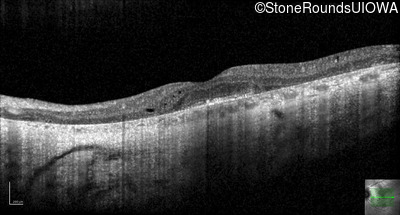

Optical Coherence Tomography - Right - 20/50 sc

Exemplar / OCT Stack